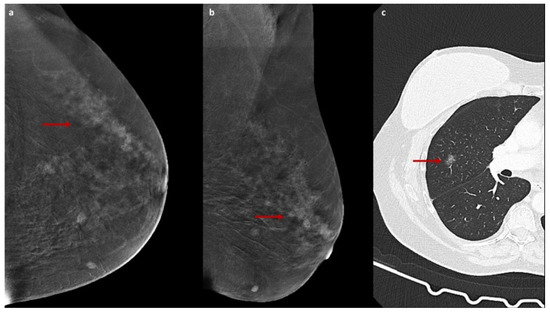

The field of radiology is undergoing a profound transformation spurred by the integration of artificial intelligence, advanced imaging techniques, and evolving clinical workflows. Specifically, contrast-enhanced mammography (CEM) has emerged as a promising tool for breast imaging, offering diagnostic performance comparable to that of MRI in certain scenarios. Meanwhile, artificial intelligence and radiomics are opening unprecedented opportunities for image analysis, prognostic modeling, and personalized medicine.

- Contrast-Enhanced Mammography: clinical applications, performance comparisons, technological innovations;